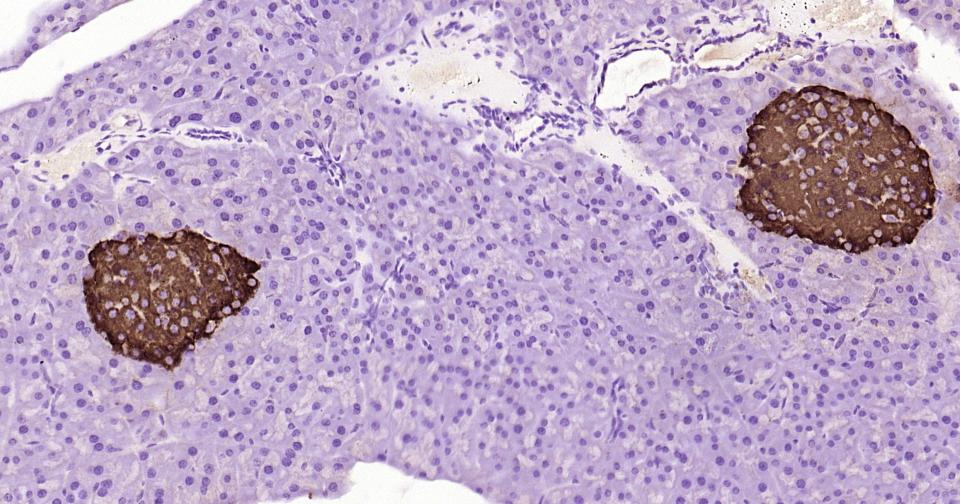

Paraformaldehyde-fixed, paraffin embedded Rat Pancreas; Antigen retrieval by boiling in sodium citrate buffer (pH6.0) for 15 min; Antibody incubation with Notch1 Monoclonal Antibody, Unconjugated(bsm-60871R) at 1:200 overnight at 4°C, followed by conjugation to the bs-0295G-HRP and DAB (C-0010) staining.